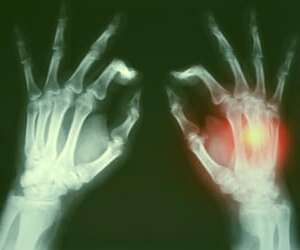

سرطان استخوان می تواند بر تمام استخوان ها تاثیر بگذارد، اما اغلب موارد، در استخوان های بلند تر پاها یا دستها وجود دارد ؛علائم اصلی عبارتند از:

- درد مداوم استخوان که در طول زمان بدتر می شود و شب ها نیز ادامه دارد.

- تورم و قرمزی (التهاب) بیش از یک استخوان است که اگر استخوان آسیب دیده نزدیک یک مفصل باشد، می تواند حرکت را دشوار کند.